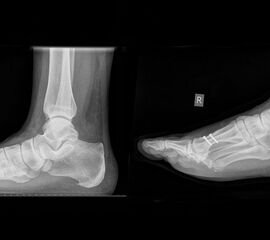

- Röntgenaufnahme des Fußes in 2 Ebenen unter Belastung und die unbelastete Schrägaufnahme (Supinationsaufnahme).

- Röntgen Fuß 2 Ebenen im Stehen und die unbelastete Schrägaufnahme.

- Intra- und postoperativ Röntgenkontrolle Fuß in 2 Ebenen zur Dokumentation. Operational zusätzliche 3 Ebene in 45° Supination.